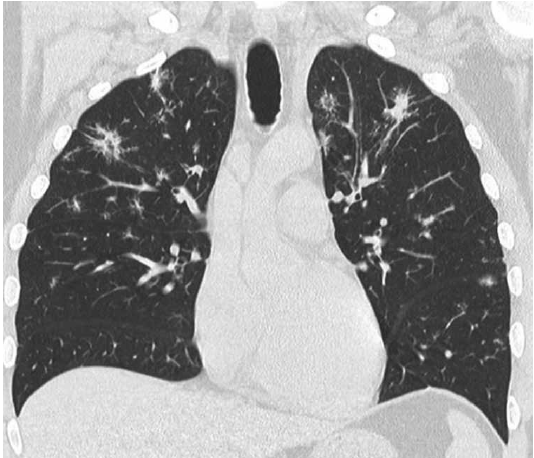

Posteriormente se realizó una tomografía computada multislice de tórax en la que se observaron múltiples imágenes ganglionares mediastinales y retropectorales y nodulillos pulmonares bilaterales a predominio en campos superiores y medios que al confluir formaban conglomerados de aspecto consolidativo (Figura 5). Se confirmó el diagnóstico anatomopatológico de sarcoidosis mediante biopsia ganglionar y endomiocárdica. Se instauró un tratamiento con corticoides endovenosos con un esquema de metilprednisolona 60 mg/día (3 dosis), seguido de 30 mg/día (3 dosis), para continuar con meprednisona 60 mg vía oral con pautas de descenso. Se decidió implantar un cardiodesfibrilador previo al alta médica.